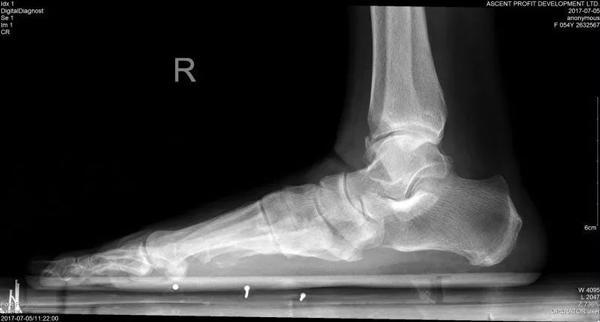

Cô Lí, nay 54 tuổi từng là giáo viên dạy tiếng Anh tại trường trung học. Từ khi còn nhỏ cô đã có một “bàn chân bẹt” – tức là gan bàn chân phẳng lì, không có vết lõm vòng cung như mọi người.

Dù đã tới nhiều bệnh viện để kiểm tra và điều trị nhưng cơn đau của cô Lí vẫn không thuyên giảm, cho tới khi cô gặp được bác sĩ Miêu Húc Đông. Bác sĩ Miêu đã tiến hành kiểm tra bàn chân cô Lí và phát hiện cô bị “hội chứng bàn chân bẹt” vì thường xuyên đứng lâu, đi giày cao gót.

Bàn chân bẹt, gan chân phẳng lì là một dạng dị tật phổ biến trên thế giới, gây ảnh hưởng nghiêm trọng đến thần kinh cột sống.

Tất cả trẻ sơ sinh đều có bàn chân không có vòm, hay còn gọi là bàn chân bẹt. Khi trẻ đến độ tuổi từ 2 đến 3, vòm bàn chân được hình thành. Cùng với hệ thống dây chằng, vòm bàn chân giúp cho chúng ta có thể chịu lực, cân bằng, đi đứng nhẹ nhàng, giúp giảm phản lực từ mặt đất dội lên khi chân di chuyển. Thông thường, những ai có hệ thống dây chằng quá lỏng lẻo sẽ dễ bị bàn chân bẹt. Đó là vì các xương ở bàn chân không được cố định tốt.

Bàn chân bình thường.

Bàn chân bẹt.